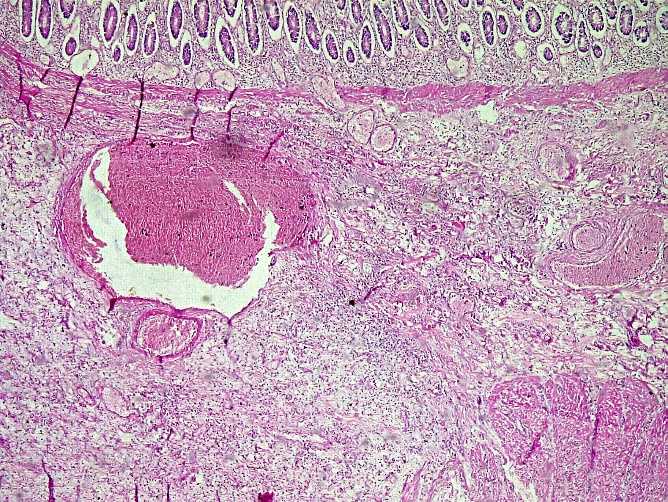

A 04-year-old girl presented with an abdominal mass in the right iliac fossa without signs of acute appendicitis. Ultrasound suggested a mesenteric cystic lymphangioma. The patient underwent laparotomy with monobloc excision of the mass, which had actually developed at the expense of the appendix.

(a)

(b)

Figure 4. (a) A macroscopic view of an 8 cm appendix with a 6 × 4 × 4 cm mass on the shiny surface of the terminal portion. (b) The cross-section shows a homogeneous, grayish-white, fibrous mass that developed at the expense of the intestinal wall.

Macroscopic examination of the surgical specimen revealed an 8 cm long appendix with a 6 × 4 × 4 cm mass at its terminal portion. The surface of the mass was uniformly smooth and shiny. In cross section, the mass developed on the intestinal wall with a homogeneous gray-white area. The mucosa was regular and unremarkable.

Microscopically, the mucosa was congested, with regular glands and no atypia. The submucosa showed abundant fibrous tissue consisting of spindle-shaped cells organized in short bundles. The stroma was loose edematous fibromyxoid with congested vessels and areas of hemorrhagic suffusion. There was an inflammatory infiltrate of lymphocytes and numerous eosinophilic polynuclear cells (Figure 4).